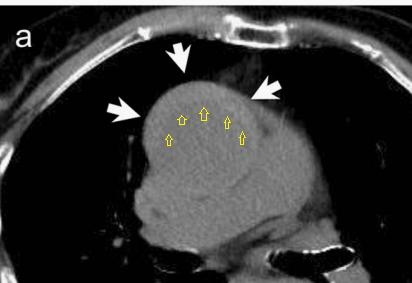

病例9

下面这个CT平扫,似乎有大问题!

图22

什么问题?似乎这里有大问题!

图23

同学,你眼神太好使了!

很可惜,这个不是问题,很多CT平扫都有这种线样阴影!

做个增强CT一看,哇,同学,你不光眼神好,运气也不是一般的好!

图24